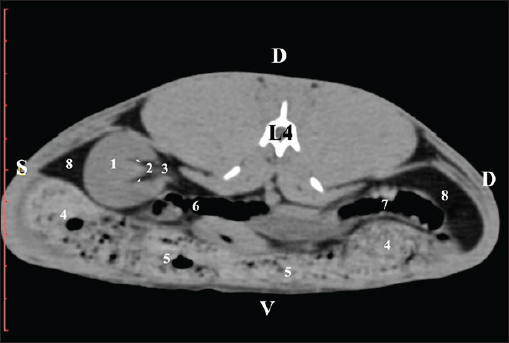

The pre-contrast anatomical scan at the L4 level provided data about the location of the renal pelvis within the renal sinus. The initial part of the pelvis renalis appeared as a distinct funnel-shaped hypoattenuated soft tissue, whose central part was widened and formed the recessus renalis. The transition of the narrowed end of the renal pelvis into the hypoattenuated left ureter was without a sharp boundary. The left kidney was in contact with the cecum, colon ascendens, and colon transversum ventrally. Crista renalis was observed as a hypoattenuated linear soft tissue finding (Figs. 10 and 11).

Fig. 10. Pre-contrast computed tomography (CT) anatomical scan of the regio-abdominis media at the cranial L4 edge level. (1) Ren sinister; (2) pelvis renalis and crista renalis; (3) ureter; (4) cecum; (5) colon ascendens; (6) colon transversum; (7) colon descendens; (8) adipose collections.

Fig. 11. Pre-contrast computed tomography (CT) anatomical scan of the regio-abdominis media at the caudal L4 edge level. (1) Ren sinister; (2) pelvis renalis; (3) ureter; (4) adipose collections; (5) cecum; (6) colon ascendens; (7) colon transversum; (8) colon descendens; (9) mesenterium; (white arrows) recessus renalis; (*) crista renalis.